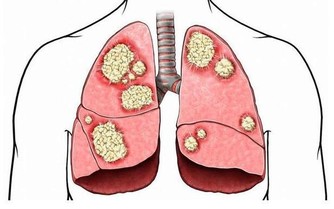

「扁 桃體結石引起的口臭並不少見,大人小孩都可能會出現」,北京中醫醫院耳鼻喉科副主任醫師姜志輝解釋。 扁桃體是人體的免疫器官,位於口咽側壁,包含有 很多隱窩,其中位於扁桃體上極的上隱窩就容易出現結石。 正常情況下扁桃腺隱窩沒有分泌物。 當扁桃體出現急慢性炎症時,就會有脫落上皮、大量淋巴細胞, 白細胞、以及各種致病菌自隱窩排出,若隱窩口堵塞而引起分泌物堆積,時間長了還會導致一些鎂、鈣等無機鹽沉積而引起結石。 這些腐敗的分泌物就會引起口 臭。

不過,這種口臭跟平時的口腔衛生沒有多大關係,刷牙、漱口等都無法達到預防和減輕扁桃體結石引起的口臭。

姜志輝提醒, 扁桃體結石只需要清除乾淨就可以了,一般不需手術。 如果結石不嚴重,在局部麻醉下用專用工具直接把結石摳出來就可以了。 如果經常扁 桃體反復發炎,總是感覺咽部異物感,並伴有口臭的人,最好及時到醫院的耳鼻喉科做專科檢查。 生活中要注意提高自身免疫力,避免局部反覆感染。

另 外,蔡立泰醫師也表示,扁桃腺結石通常看起來像白色或微黃色的小石頭,有時候吐出來時,可以把這些小石頭壓碎,並出現臭臭的味道。扁桃腺結石目前 大多認為是由食物的殘渣及壞菌卡在扁桃腺表面的隱窩中所形成。有些人會感覺到喉嚨卡卡的感覺,嚴重的患者更可能出現頭痛、咽喉疼痛、吞嚥困難、耳朵痛癢、 甚至嘔吐等情形。也因為這些細菌和食物的殘渣以及部分壞死組織的鈣化,所以可能在講話時散發出一些腐爛的臭味,也就是我們所謂的口臭。

造成扁桃腺結石的原因,除了長期發炎導致以外,口腔清潔不夠、喜愛吃刺激食物、油炸物、作息不正常、熬夜等等都是要注意的危險因子。